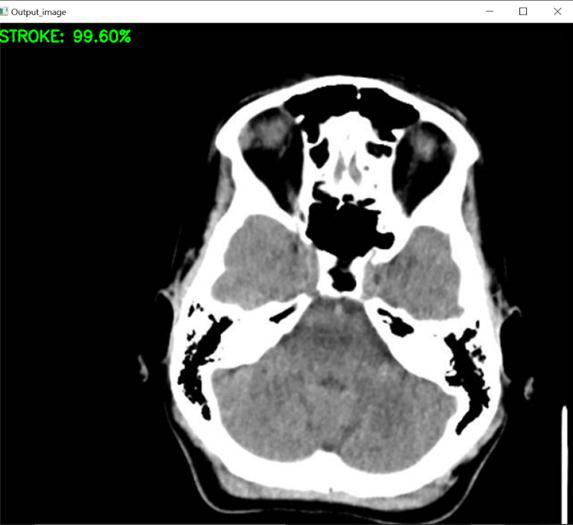

RESULT

TheproposedsystemaccuratelydiagnosestheincidenceofahaemorrhageinthehumanbrainbyutilisingCT scanimages,andtheoutputissuccessfullyachieved.